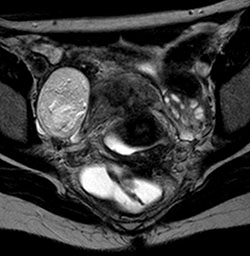

O curso foca em uma abordagem prática e atualizada da ressonância magnética da PELVE FEMININA, com base nos principais consensos de ENDOMETRIOSE e metodologia de APRENDIZADO BASEADO EM CASOS RADIOLÓGICOS (ABC-RAD).

Em cada encontro será abordado um tema dentro do assunto ENDOMETRIOSE, com discussão dos casos selecionados e EXPLICAÇÃO DAS IMAGENS, com acesso ao LAUDO DETALHADO no final de cada caso.